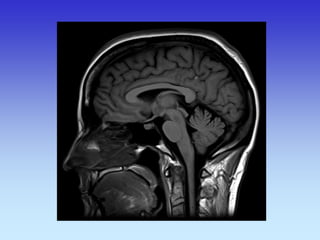

Sagitalni presjek

Genu of Corpus

Callosum

Hypophysis

Body of corpus callosum Thalamus

Splenium of Corpus callosum

Genu of corpus callosum

Pons

Superior Colliculus

Inferior

Colliculus

Nasal

Septuml

Medulla

Cingulate Gyrus